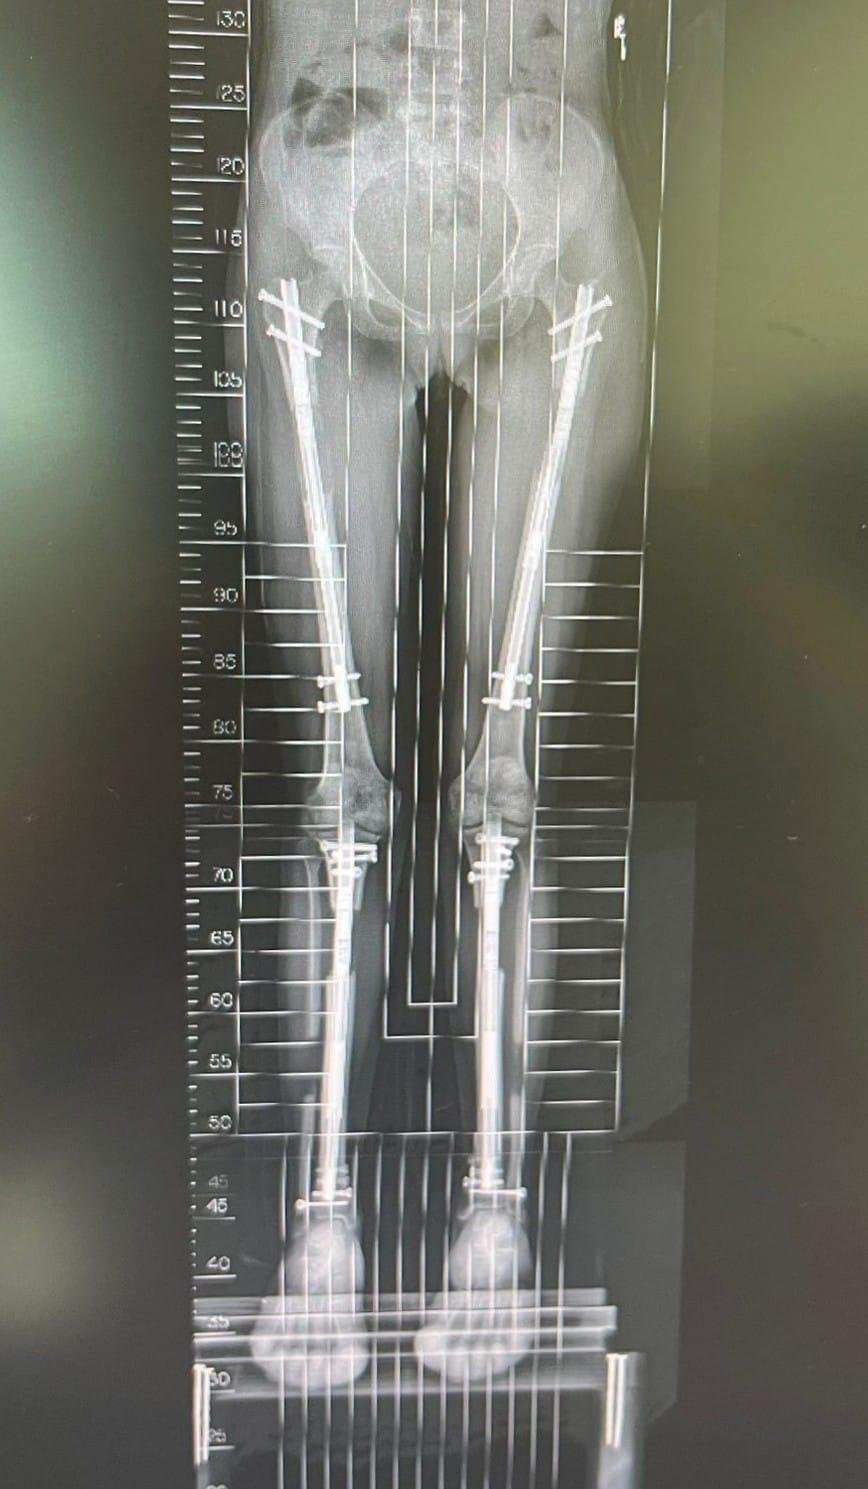

You can grow 15-18cms with our limb lengthening surgery

LON Method.

Grow 10cm on femur, and 8cm on tibia with the LON method.

Precise 2 Method.

Achieve up to 9 cm on femur, or 7 cm on tibia with Precise 2.

Limb lengthening surgery is a specialized orthopaedic procedure designed to gradually increase height or correct leg length discrepancies. The process is carefully controlled and performed in stages, using advanced technology to ensure safety and precision. The surgery stage primarily focuses on the femur (thigh bone) or tibia (shin bone), or in some cases, both, depending on the patient’s goals. Patients undergo a thorough evaluation to determine the best surgical method, ensuring that the procedure is tailored to their specific needs.

During the lengthening phase, the bone is gradually pulled apart, typically by about 1 millimetre per day. This slow, steady process stimulates the body’s natural ability to grow soft tissue, nerves, and blood vessels, ensuring that the bone regenerates properly. The lengthening is closely monitored through regular follow-ups and X-rays to ensure that the bone grows in a straight, healthy manner. Patients must engage in physical therapy to maintain mobility and flexibility, preventing joint stiffness during the process.